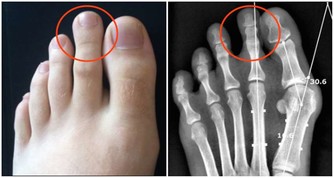

肺部是呼吸系統重要的器官,人們的輕鬆的呼吸、乾淨的血液都依靠肺部的運行。當肺部出現了健康問題,對於整個身體健康是有很大影響的,甚至會危及到生命,所以及時知曉肺部的求救信號是非常重要的。睡覺時有哪些異常情況是肺在求救呢?接下來讓我們一起來了解一下。

肺部受損是一件比較重大的事,出現了肺部疾病也不要拖延,一定要及早治療,這樣才能把後果盡量的降到最低。